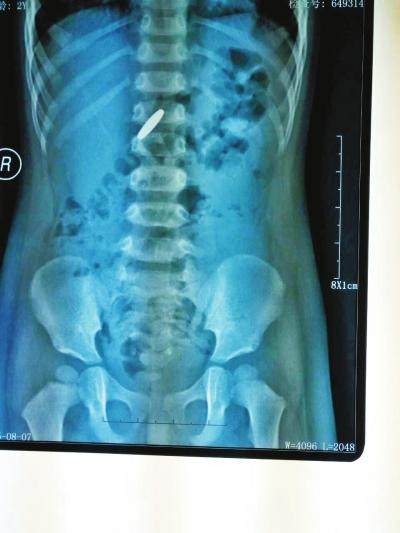

常见的异物吞食有哪些?最近西安市儿童医院做了近三年从宝宝体内取出部分异物的统计。纽扣电池、枣核、玩具配件、钉子、塑料棒、缝衣针、玻璃弹珠应有竟有,其中最多的就是硬币。

硬币拍片在人体的位置